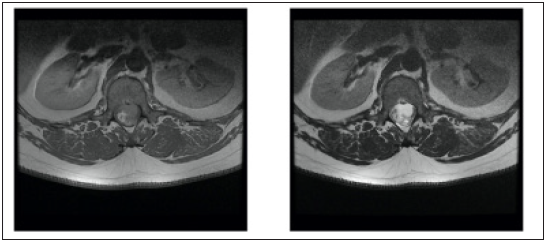

A 34-year-old male patient presented with a few months’ history of back pain. The patient had been treated with non-steroidal anti-inflammatory drugs (NSAIDs) for a few weeks in an outpatient clinic by a neurologist. Despite the treatment the back pain became constant and the patient started experiencing weakness in both legs while climbing stairs. The patient was referred for magnetic resonance imaging (MRI) of the thoracolumbar region (Figure 1 & 2). The MRI scan showed a multicompartmental heterogeneously enhanced intramedullary lesion located along Th12 and L1 vertebral bodies. A computed tomography angiography scan was also conducted and revealed neither spinal dysraphism, nor pathological vascular nidus. The patient was admitted to the Department of Neurosurgery in our hospital with spastic lower paraparesis (3 out of 5 on the muscle strength scale), bilateral positive Babinski sign, bilateral hypoesthesia below L1 dermatome, proprioceptive dysfunction in the lower extremities. Surgical treatment was suggested aiming for neural decompression, histologic verification and resection of the lesion. Laminectomies of Th12, L1 and partially on Th11 and L2 were conducted. Motor evoked potentials (MEPs) were monitored during the operation (Figure 3). The tumor was partially removed due to its adherence to the surrounding spinal cord and temporary deterioration of MEPs during surgical resection (Figure 4). The dura mater was closed with a watertight running suture and sealed with autologous fibrin glue. The histological examination revealed a mature teratoma (Figure 5). The patient had an uneventful postoperative period and was ambulating independently/muscle strength 5 out of 5/ on the 7th postoperative day. Control MRI was conducted 1 month postoperatively (Figure 6).

Figure 1: Preoperative axial reconstructions or T I -weighed MR-images with contrast enhancement and T2 -weighted M R-images of the spine at L1 vertebral body. A heterogenous cystic lesion with scarce contrast enhancement is observed is Th12-Ll level